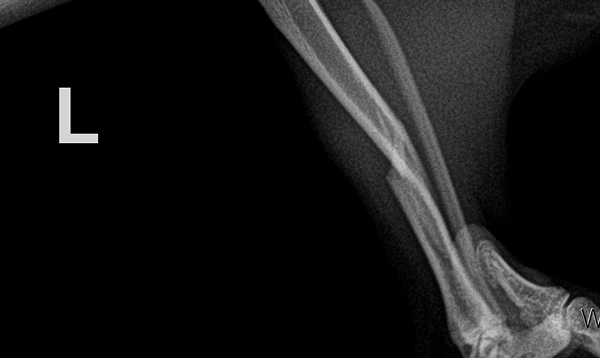

수술케이스 ④ 블*강아지 - 경골 복합골절

수술케이스 4 before BEFORE